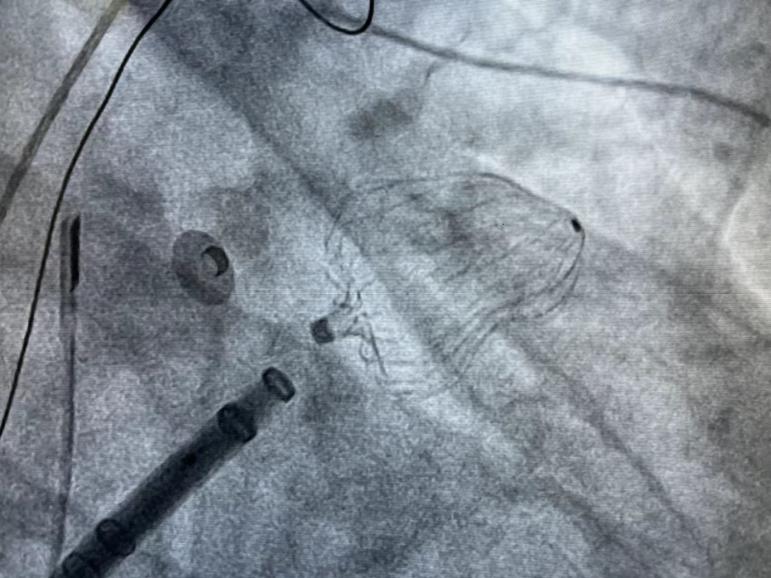

此例手术由韩稳琦博士和酉鹏华博士通过ICE指导下进行,通过ICE精准构建心脏模型、直视下穿刺房间隔,结合三维标测系统,精准、高效地完成双侧肺静脉隔离。后通过ICE及左心耳造影评估左心耳特征为下缘短,上缘折角大的短颈鸡翅型心耳,利用12F导引系统鞘管和猪尾导管在DSA肝位下同时造影,测量左心耳开口25.12mm,最大可用锚定区深度19.71mm,最终选择31mm规格watchman FLX封堵器的植入。ICE从不同角度检查即将释放的WATCHMAN FLX左心耳封堵器,观察封堵器位置、露肩、残余分流和压缩比情况,明确封堵器位置合理,无明显露肩,完全封堵无残余分流,封堵器位置良好。随后在ICE下观察及DSA透视下作牵拉试验,直到最后一次牵拉与前一次牵拉比较无位置改变,压缩比无明显变化,符合封堵器释放的“PASS”原则后完全释放封堵器。

4 Watchman FLX封堵器释放